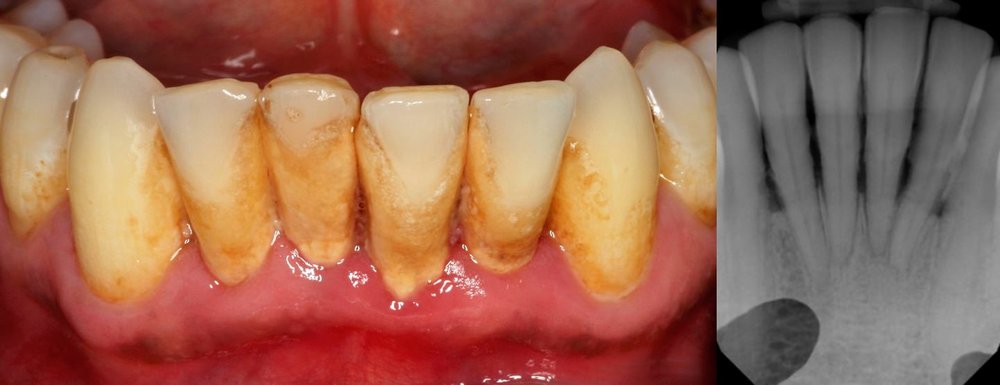

Though deep cleaning teeth prices are higher than regular cleanings, it’s an investment in your oral health and an attempt to. What is the average cost of a dental cleaning? Why do you need deep teeth cleaning?

Dental deep cleaning may cost $150 to $350 if you don’t have dental insurance. Prices for a dental deep cleaning vary by provider and location. The total expense of dental cleaning appointments can change.

How much does a dental deep cleaning cost with insurance. Usually between $200 and $400. Deep cleaning may cost between $140 and $300, depending on your location and your dentist.

Cleanings done by a dental hygienist may cost less than cleanings done by a dentist. For a dental deep cleaning treatment, including dayton dental scaling and root planing, dentists usually divide the mouth into four quadrants, and clean one quadrant per visit.the course of treatment averages between $750 and $1,200, though this cost is dramatically affected by the. If you do not have dental insurance coverage, there are other ways in which you can spend less for oral care treatment:

Periodontal treatment will cost more, compared to a preventative option. With insurance, they are usually $0. The cost of oral healthcare procedures like a dental deep cleaning isn’t out of reach.